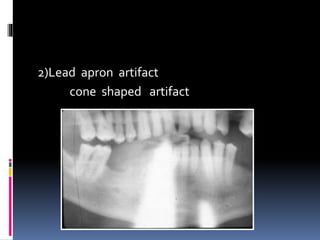

2)Lead apron artifact

cone shaped artifact

 Thyroid collar